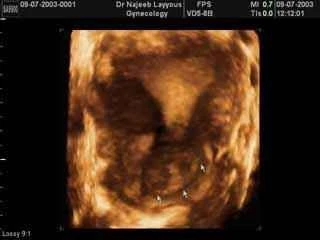

يمكن تشخيص الألياف الرحمية بواسطة الفحص السريري الذي يعتمد على شكوى المريضة من حيث الأعراض التي تعاني منها ، والفحص من قبل الطبيب، إلا إن هذا النوع من التشخيص لا يمكن الاعتماد عليه خوفاً من اختلاط التشخيص بأمراض أخرى تشارك الألياف الرحمية بنفس الأعراض مثل مرض البطانة الرحمية الهاجرة أو أكياس المبيض ولهذا السبب يجب أن يجرى فحص بواسطة جهاز الالتراساوند (الموجات فوق

الصوتية)، لكل مريضة تشكو من نزيف مهبلي أو آلام شديدة في البطن عند زيارتها الأولى للطبيب

الصوتية)، لكل مريضة تشكو من نزيف مهبلي أو آلام شديدة في البطن عند زيارتها الأولى للطبيبوفحص الالتراساوند المهبلي هو فحص سريع ويعطي معلومات دقيقة إلا أن ذلك يتطلب مهارة ومعرفة علمية بما هو طبيعي وما هو غير ذلك من قبل الطبيب المعالج، ومراقبة ذلك على جهاز الالتراساوند لإعطاء صورة أوضح ومعلومات أدق ولمنع أي التباس في التشخيص كما يمكن النظر في داخل الرحم بواسطة المنظار الرحمي

هناك حالات تتشابه في تشخيصها مع الألياف الرحمية وأهمها كما ذكرنا سابقاً مرض البطانة الرحمية الهاجرة حيث تتداخل بطانة الرحم مع جدار الرحم مما يؤدي إلى زيادة في سماكة جدار الرحم وتضخم في الرحم وهذا يمكن ملاحظته من خلال فحص الالتراساوند في حين ترى الألياف كمناطق دائرية لها حدود واضحة، فقبل الانتقال للمرحلة العلاجية يجب أن يكون التشخيص قائماً على أساس من الثقة حيث تتحكم في العلاج عوامل منها : حجم الليف وموقعه من الرحم ومدى حدة الأعراض التي يسببها

هل يظهر تليف الرحم في السونار؟

نعم يتم تشخيصه على السونار اذا كان الفاحص شخص ذو خبرة باستخدام جهاز السونار